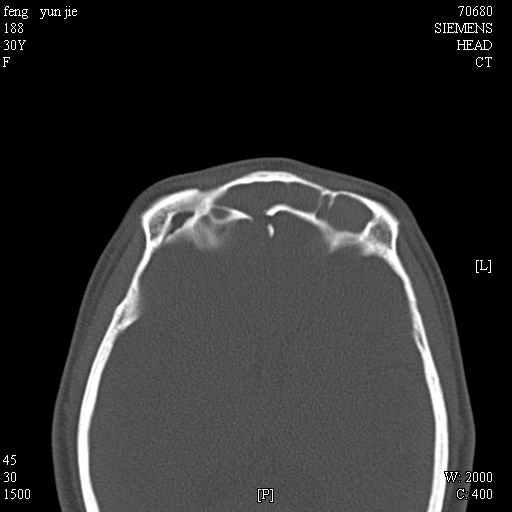

女,37岁,多年前鼻骨骨折过,现在穿刺有炎性分泌物

2、额窦粘液囊肿(右侧水平额窦突入眶内上方)可能性大。

1)左侧鼻骨骨折(陈旧性)。2)双侧额窦及双侧筛窦炎症,伴右侧额筛窦黏液囊肿突入右侧眼眶。

额窦粘液囊肿(右侧水平额窦突入眶内上方)可能性大

考虑额窦粘液囊肿可能性大。